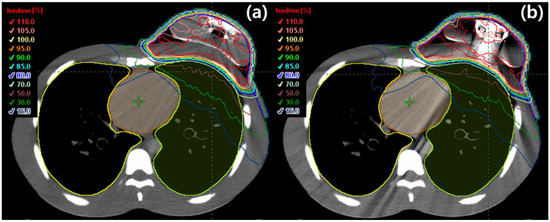

| Parameter | RFID Port | Metallic Port | Percentage Difference |

|---|---|---|---|

| PTV | |||

| HI | 1.31 | 1.32 | 0.76 |

| CI | 0.95 | 0.95 | 0 |

| QOC | 0.92 | 0.90 | 2.19 |

| V95, % | 98.40 | 98.10 | 0.30 |

| V107, % | 71.70 | 80.80 | 11.93 |

| Heart | |||

| V5Gy, % | 22.91 | 29.75 | 25.97 |

| V10Gy, % | 6.54 | 11.46 | 54.66 |

| V15Gy, % | 2.77 | 4.97 | 56.84 |

| V20Gy, % | 1.39 | 2.75 | 65.70 |

| V30Gy, % | 0.23 | 0.68 | 98.90 |

| Dmean, Gy | 4.08 | 4.92 | 18.66 |

| Ipsilateral lung | |||

| V5Gy, % | 36.08 | 38.86 | 7.41 |

| V15Gy, % | 12.85 | 14.73 | 13.63 |

| V20Gy, % | 7.50 | 8.67 | 14.47 |

| V30Gy, % | 1.87 | 2.36 | 23.16 |

| Dmean, Gy | 6.43 | 6.94 | 7.62 |

| Contralateral lung | |||

| Dmean, Gy | 2.44 | 2.51 | 2.82 |

| Whole lung | |||

| V20Gy, % | 3.69 | 4.25 | 14.10 |

| Dmean, Gy | 4.40 | 4.68 | 6.16 |

| Contralateral breast | |||

| Dmean, Gy | 2.58 | 2.68 | 3.80 |